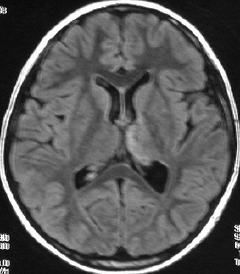

35歳,側頭葉てんかんで発症した右側頭葉の乏突起膠腫 グレード2です。全摘出して化学療法4コースと54グレイの局所放射線治療 generous local fieldを行いました。7年後に同じ部位に再発して摘出したところ退形成性乏突起膠腫 グレード3となっていました。手術摘出して,テモゾロマイド化学療法で維持療法をしていました。

その2年後の画像です。右小脳半球に再発しています。右側頭葉腫瘍との連続性は全くありませんでした。脳幹部にも腫瘍はありません。遠隔再発 remote recurrenceというもので,星細胞系腫瘍 astroytic tumor AAやGBMではよく知られている現象です。乏突起膠細胞系腫瘍でもまれにみられます。